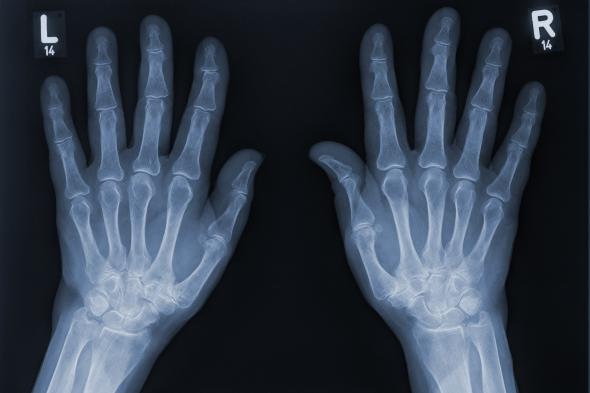

Radiografía de dos manosGetty Images

Pero, ¿alguna vez te has preguntado por qué este dedo es tan diferente al resto? Mientras los demás tienen tres huesos o falanges, el pulgar solo tiene dos. Y esta diferencia no es casualidad, sino el resultado de un largo proceso evolutivo que cambió para siempre la forma en que los humanos interactúan con el mundo.

Cada dedo tiene tres falanges (distal, media y proximal), excepto el pulgar, que solo cuenta con la proximal y la distal. Esta diferencia, junto con los músculos, tendones y ligamentos que lo acompañan, permite una destreza única que ninguna otra especie posee.